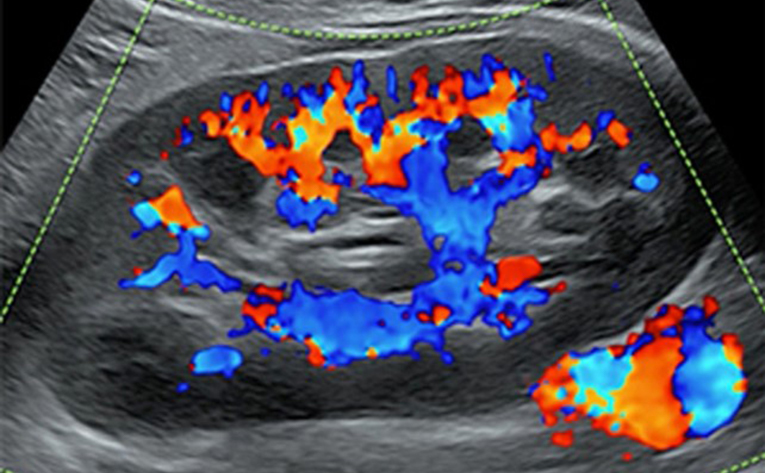

초음파기기